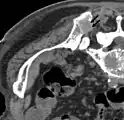

- Comparaison scanner/IRM pour des métastases ostéolytique d'un cancer du sein dans la colonne vertébrale

Scanner sagittal reconstruit, représentation dans la fenêtre osseuse. Comme la patiente avait des métastases dans toutes les régions du corps, elle ne pouvait pas lever les bras pour l'examen, ce pourquoi les mains sont présentées.

Scanner sagittale, parties molles. Outre les métastases dans la colonne vertébrale, qui envahissent en partie le canal médullaire vers l'arrière, métastases aussi dans le sternum. Plus des métastases dans le foie.

IRM natif avec pondération T1.

IRM sagittal natif avec pondération T1. On voit clairement l’extension jusqu'aux lames vertébrales.